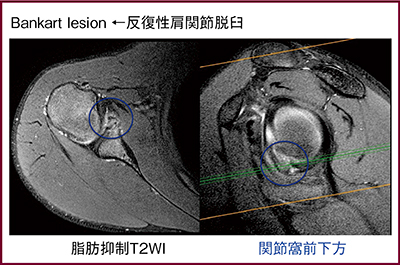

読影では,患者の臨床所見から損傷箇所を予想して(待ち伏せて)おく必要がある。中高年の疼痛肩であれば腱板断裂が疑われるので棘上筋腱停止端,反復性脱臼肩であればBankart損傷の前下方関節窩(図4)やHill-Sachs損傷の骨頭上背側,スポーツ障害肩であればSLAP損傷の後上方関節唇,というように見るべき場所を考えて読影する。

図4 Bankart損傷の描出